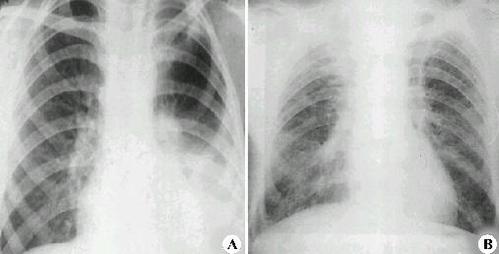

间质性肺炎x线图片,间质性肺炎x线

急性间质性肺炎的诊断与鉴别诊断

1x线胸片检查,ct扫描一般情况通过x线胸片检查,间质性肺炎晚期较容易

间质性肺炎x线

间质性肺炎胸片

间质性肺炎图片

间质性肺炎影像学